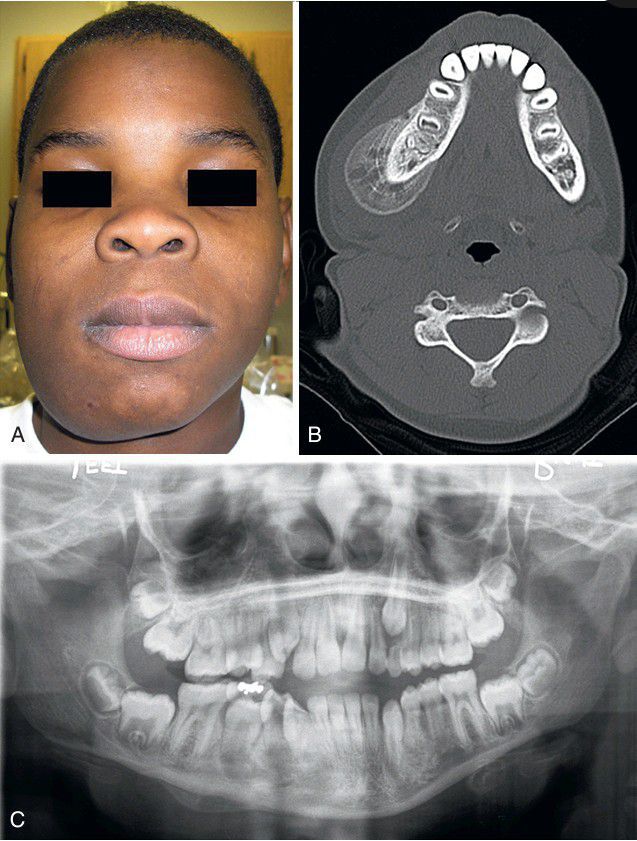

A, Firm swelling of the lateral and inferior border of the right mandible that arose after traumatic injury. B, Computed tomography (CT) image demonstrating new periosteal bone growth with onionskin laminations. C, Panoramic radiograph exhibiting new periosteal bone formation along the right inferior border of the mandible.